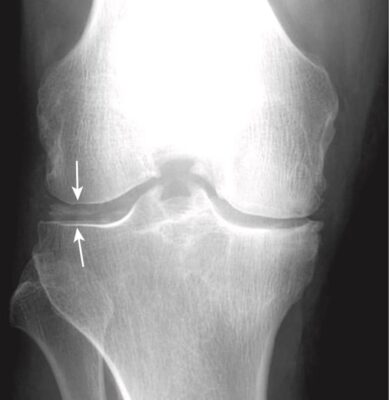

Hình 11. Chondrocalcinosis (Vôi hoá sụn). Chondrocalcinosis chỉ đề cập đến sự vôi hóa của sụn khớp (mũi tên trắng) hoặc sụn sợi và hầu hết không có triệu chứng. Nếu bệnh nhân này bị sưng, nóng, đỏ đau cấp tính, và hạn chế vận động khớp gối thì tình trạng này được gọi là giả gout.